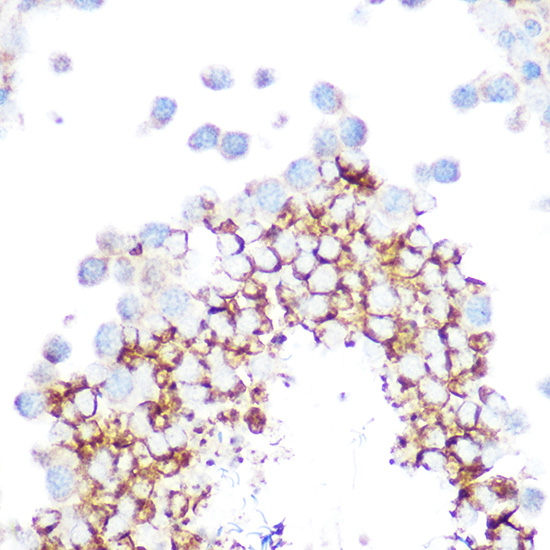

Immunohistochemistry of paraffin-embedded rat testis using GPX4 Rabbit pAb.

Immunohistochemistry of paraffin-embedded mouse testis using GPX4 Rabbit pAb.